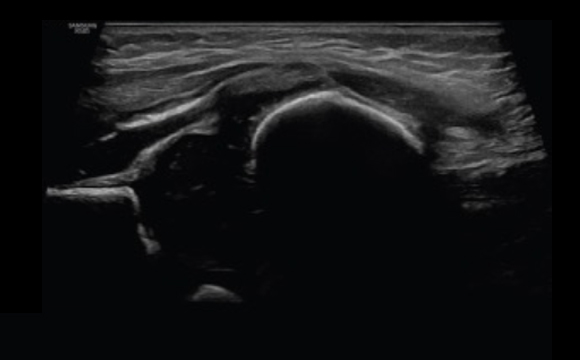

ShadowHDR™ applica selettivamente ultrasuoni ad alta o bassa frequenza per identificare le zone in ombra, come la testa o la colonna vertebrale del feto, dove si verifica l'attenuazione e le compensa permettendo una maggiore visibilità del tessuto.

Testa Neonatale a